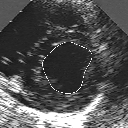

DETECTION AND TRACKING OF ANATOMICAL STRUCTURES USING DEFORMABLE TEMPLATES AND A NOISE MODEL ESTIMATION IN AN ECHOGRAPHIC SEQUENCE

In this work, we present a new method to shape-based segmentation of deformable anatomical structures in medical images and validate this approach by detecting and tracking the endocardial border in an echographic image sequence. To this end, a global prior knowledge of the endocardial contour is captured by a prototype template with a set of admissible deformations to take into account its inherent natural variability over time. In this approach, the data likelihood model rely on an accurate statistical modeling of the grey level distribution of each class present in the image. The parameters of this distribution mixture are given by a preliminary estimation step which takes into account the distribution shape of each class. Then the tracking problem is stated in a Bayesian framework where it ends up as an optimization problem. This one is then efficiently solved by a genetic algorithm combined with a steepest ascent procedure. This technique has been successfully applied on synthetic images and on a real echocardiographic image sequence. This method seems to be particularly well suited to handle ultrasound images with strong speckle noise on which edge information cannot be exploited. Finally, the local and global minimization procedure we propose is fast, robust and do not require initialization of the template close to the desired solution. Initialization may be defined at random, leading to segmentation and tracking procedure that are completely data driven. (slides)

Figure 1:   Tracking of the endocardial contour in a medical echographic sequence at different time frames during the cardiac cycle. From top left to bottom right : frame 1, 4, 6, 9, 12, 13, 18, 20, 27, 30, 35, 40, 41, 44, 46.